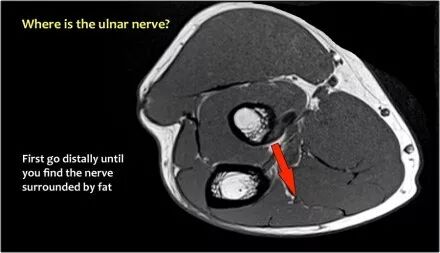

尺神经:在这里,我们看到了肘管内的尺神经。尺骨侧支带的后带形成隧道的底部,而支持带形成屋顶。

该患者有尺神经神经病变。肘管综合征是一种常见的周围神经病变。它产生于肘管内尺神经,其中该神经传递肘管支持带的下方的压缩。

肘管综合征的可能原因● 过度使用● 由于纤维组织中的先天性松弛,尺神经半脱位● 肱骨骨折伴游离体或愈伤组织形成● 由上髁或鹰嘴引起的关节炎● 存在肌肉异常● 软组织肿块:神经节,脂肪瘤,骨软骨瘤,继发于类风湿性关节炎的滑膜炎,感染(例如结核病)和出血。

当他们将尺神经带出隧道时,他们把它放在哪里,它可以是皮下,肌肉下或肌肉内。

因此,当我们回到图像时,您会发现很难找到神经。任何这些皮下结构都可以是转位神经。一种方法是远端跟随结构,直到你发现远端的尺神经位于由脂肪包围的前臂近端的正常位置。然后当你向近端跟随它时,你会发现这是皮下移位。

在这种情况下,有神经炎。神经增大。在T2W图像上有高信号。另一个标志是在矢状图像(箭头)上看到的束的不均匀扩大。